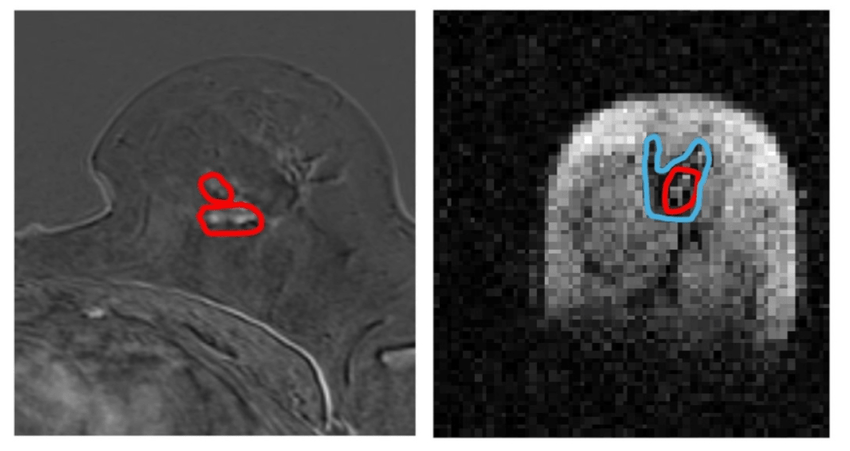

Read more on the DIETRICH Study, led by Aberdeen Cancer Centre Co-Director, Professor Anne Kiltie, and her colleague Professor Ananya Choudhury, University of Manchester, and funded by Prostate Cancer UK